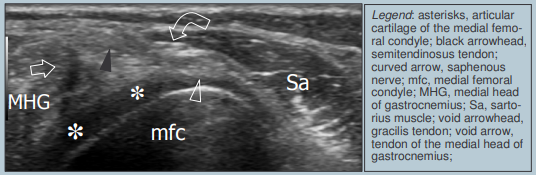

Tendons Médiaux

**Bourse Semimembraneuse-gastrocnemien **